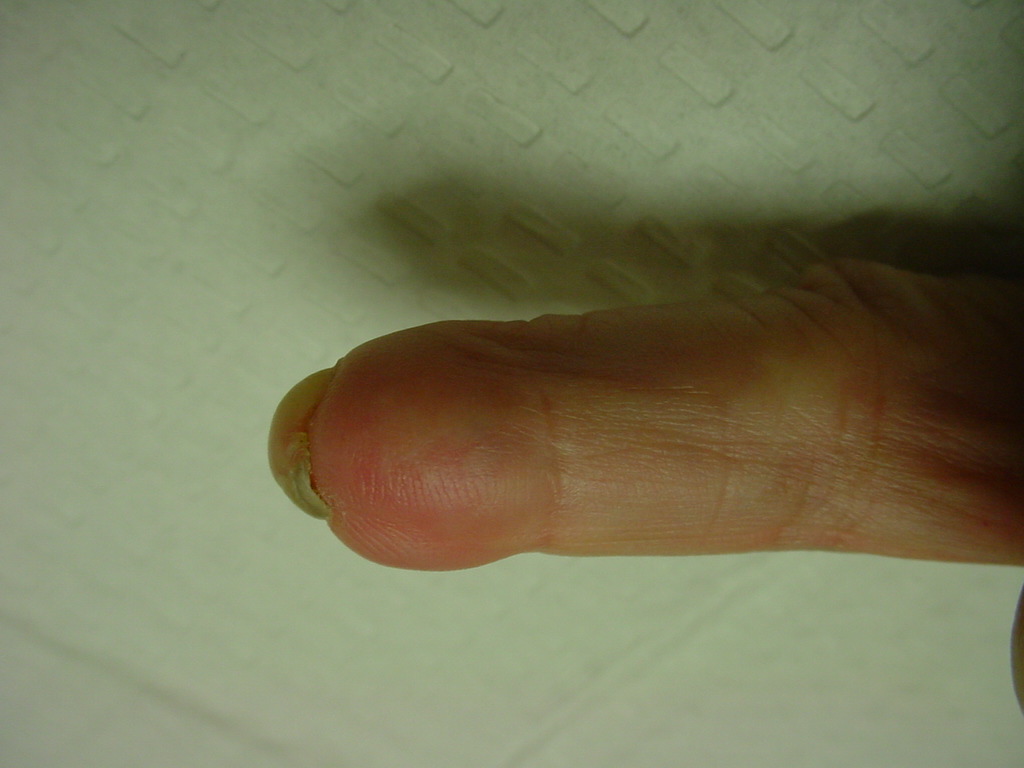

Following fingertip amputation, Hook nail deformity can result from loss of adequate supporting length of distal phalanx. This reduces the radius of curvature of the nail, and in extreme cases, the nail plate curves tightly over the end of the fingertip. One type of reconstruction involves lengthening the tip with a bone graft and skin flap, sometimes referred to as the "antenna procedure" because of the appearance of temporary pins protruding from the fingertip. One problem with this approach is that the distal bone graft may resorb slowly over the years that follow.

The small fingertip has a squared off contour and hook nail deformity following a traumatic amputation. Reconstruction was performed using a volar advancement flap and bone graft:

As the bone graft resorbed, the contour became more bulbous, and several years later was revised with excisional W-plasties.

The tip graft progressively resorbed, and by six years after reconstruction, the hook nail deformity has recurred completely.